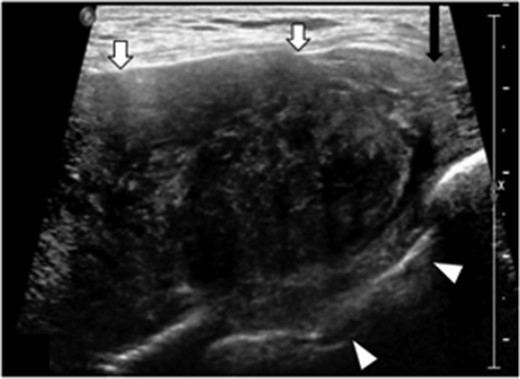

Ultrasound revealed a well-defined, heterogeneously, hypoechoic mass abutting the superior medial portion of the intact implant (Fig. 2). The lateral aspect of the mass demonstrated a characteristic ‘fascial-tail’ sign described by Huang et al. [8] as the linear extension of the tumor along the fascial planes diagnostic of fibromatosis. The mass extended into the intercostal space posteriorly. There was evidence of increased vascularity. The axilla was evaluated and showed no suspicious axillary lymphadenopathy. Magnetic resonance imaging (MRI) without contrast demonstrated an 8.1 × 4.7 × 7.1 cm3 slightly lobulated mass abutting the un-ruptured silicone breast implant (Fig. 3). The mass extended into the anterior intercostal space between the second and third ribs, with no definitive involvement of the ribs. On T1 weighted sequences, the lesion was heterogeneous and had low signal; signal intensity was hyperintense on gradient-echo imaging. The pectoralis muscle was seen extending over the mass but without definitive involvement.

Transverse targeted ultrasound image of palpable breast mass show a large heterogeneously, hypoechoic mass with internal vascularity, well defined (white arrows). Mass extends between the ribs into the intercostal space (arrowheads). Beak like appearance at the lateral margin (characteristic ‘fascial tail’ sign, black arrow).